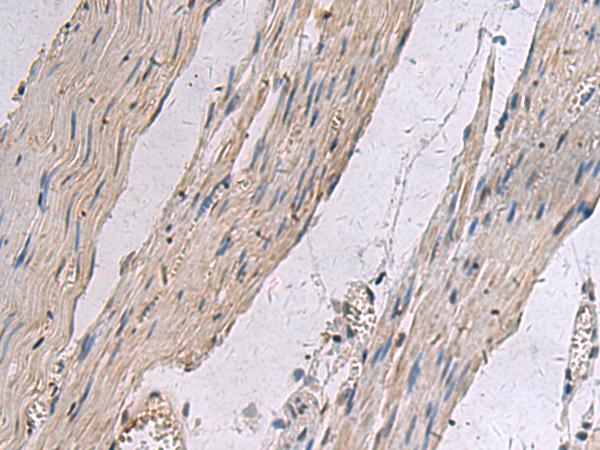

IHC positive control:

Human esophagus cancer

IHC Recommend dilution:

25-50